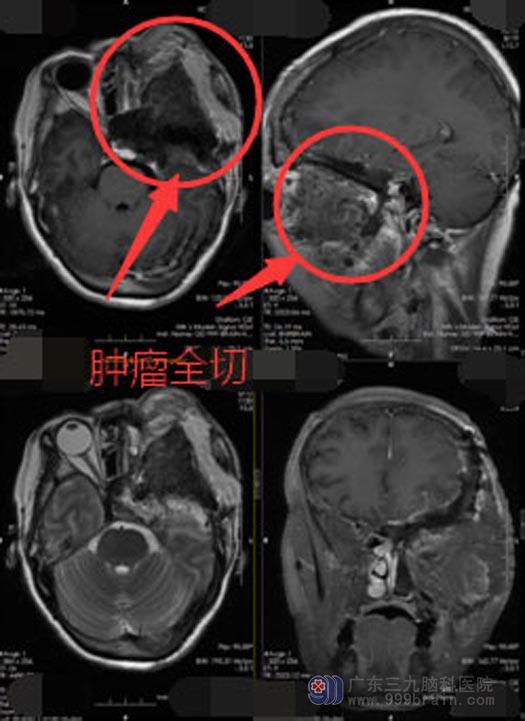

蔡阿姨的术前诊断明确,医院副院长、神经外五科主任鲁明带领团队经过详细的计论,评估手术中可能发生的风险,制定了周密的手术方案。家属知情同意后,由鲁明主刀联合口腔科专家行“左侧前中颅底肿瘤扩大切除术+颅底切除+颧骨颧弓切除+眼眶切除+眶内容物切除+上颌骨部分切除+左侧颈内动脉-桡动脉-大脑中动脉主干血管搭桥术+颅底缺损左侧股骨前外侧皮瓣转移修复+左侧桡动脉切除术+气管切开术”,手术顺利,经过连续21个小时的奋战,终于将肿瘤全部切除,术后无活动出血。

目前蔡阿姨神志清醒,四肢肌肢力V级,家属非常满意手术效果。